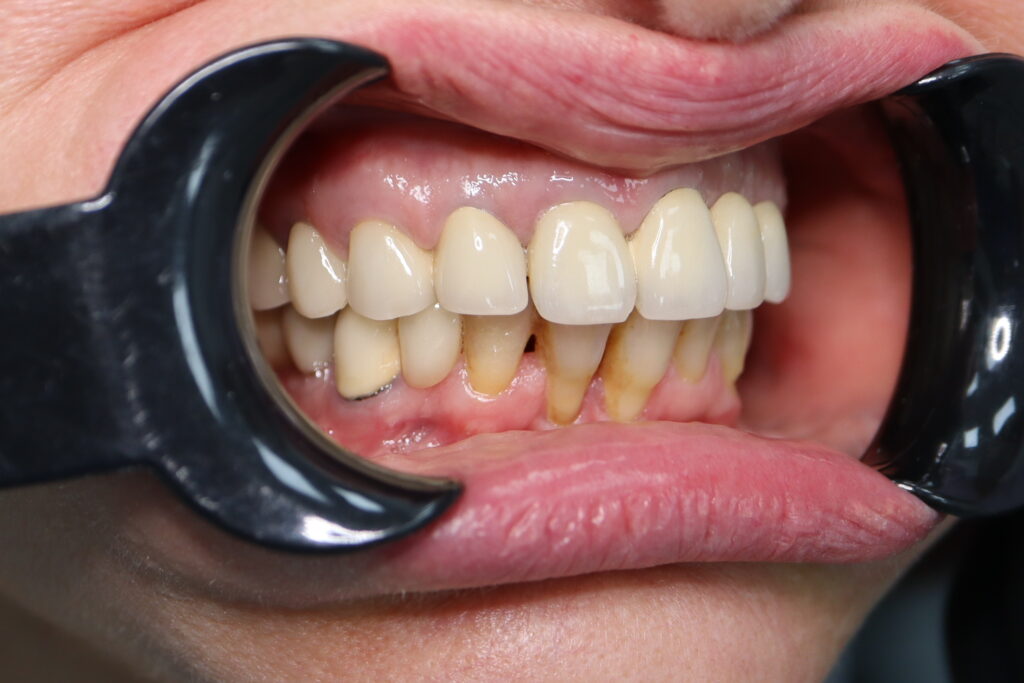

Ситуация до лечения

Жалобы: Пациент обратился к нам с целью установить имплантаты аналогичные, установленным 6 лет назад в другой клинике.

Диагноз: Частичная вторичная адентия верхней челюсти.

пациент до имплантации